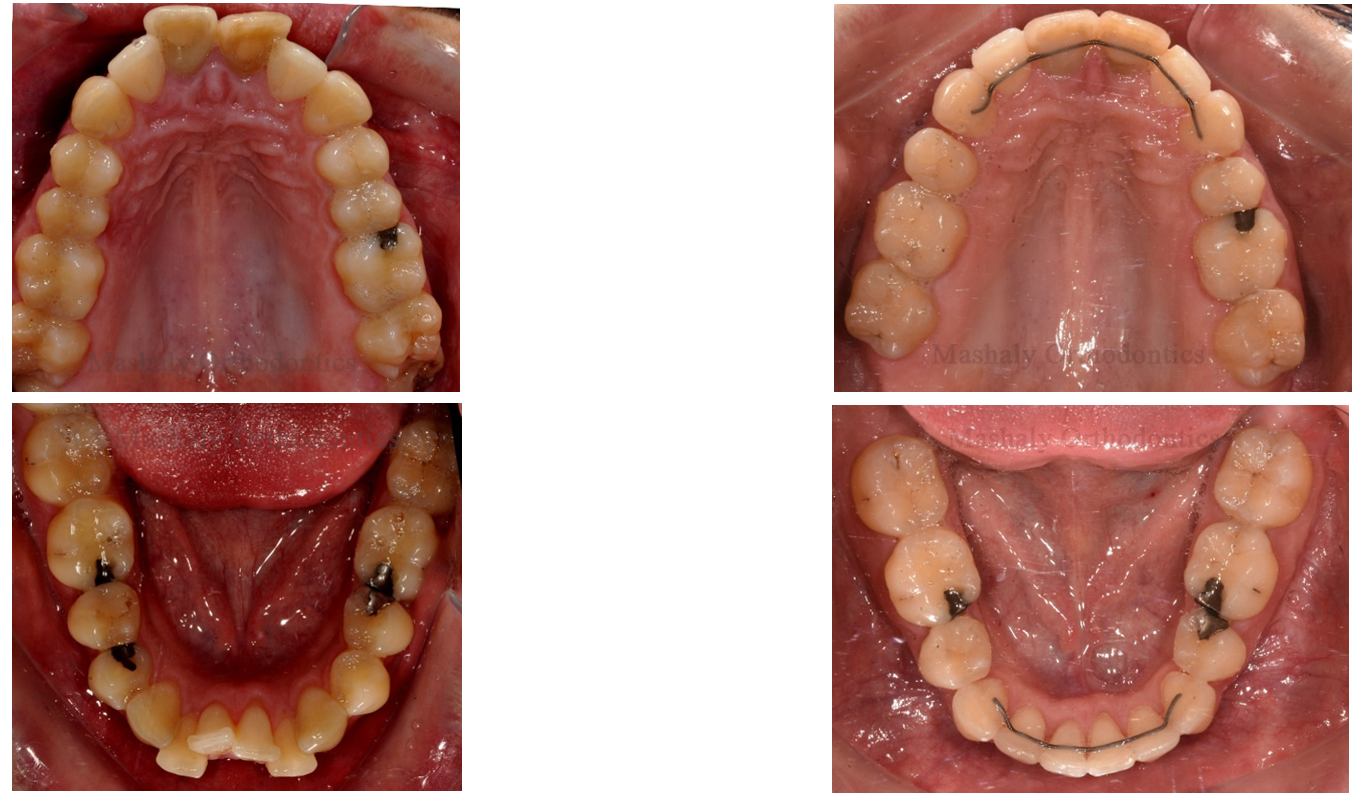

1.Traditional Metal Braces :

Traditional metal braces are the most common type of braces and are smaller and more comfortable today than ever before. Made of high-grade stainless steel, metal braces straighten your teeth using metal brackets and archwires. With metal braces, you have the option of adding colored elastics (rubber bands) for a more unique and colorful smile.

2-Ceramic Braces

Ceramic braces are made of clear materials that are less visible on your teeth than metal braces. For this reason, ceramic braces are used mainly on older teenagers and adult patients who have aesthetic concerns. While they are visually less prominent, they do require more attention to oral hygiene as ceramic braces are larger than metal braces. The only drawback to ceramic brackets is that they are more fragile, and the elastic ties can discolor between orthodontic visits with certain foods and smoking.